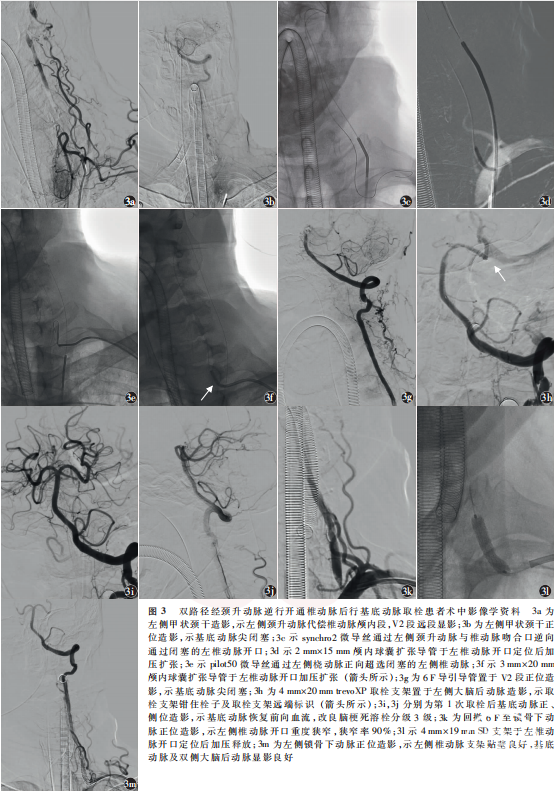

男,76岁,因“意识不清10h”于2022年8月5日18:12入住山东第二医科大学附属临沂市人民医院神经内科。患者于入院前10h突然出现意识不清,呼唤无反应,疼痛刺激可见皱眉,无发热、呕吐、肢体抽搐、大小便失禁。15:44于当地医院就诊,行脑血管造影见右侧椎动脉非优势,左侧椎动脉开口闭塞,诊断椎动脉闭塞性脑梗死,尝试行椎动脉机械取栓未成功,遂转入我院。患者既往高血压病史10年,平素不规律服药治疗;否认糖尿病、冠心病、卒中史。卒中门诊神经系统体格检查:浅昏迷,言语不合作,双侧眼球居中,双侧瞳孔直径3mm,对光反射灵敏;四肢肌力0级,四肢肌张力减低,双侧Babinski征阳性,美国国立卫生研究院卒中量表(NIHSS)评分31分;头部CT血管成像(CTA)、CT灌注示基底动脉尖闭塞(图1a),双侧小脑、脑干低灌注,存在较大面积缺血半暗带(图1b),诊断为脑梗死、基底动脉闭塞。拟行急诊血管内介入治疗。患者于2022年8月5日18:55全身麻醉后穿刺右侧股动脉,置入8F动脉鞘,送入5F单弯导管行双侧锁骨下动脉造影,示右侧椎动脉非优势(图2a),左侧椎动脉开口闭塞,未见明显残端,左侧颈升动脉代偿椎动脉颅内段显影,基底动脉显影差(图2b,2c),左侧颈总动脉造影示后交通开放,代偿大脑后动脉显影(图2d);单弯导管超选左侧锁骨下动脉,利用synchro2微导丝(0.014英寸×300cm;1英寸=2.54cm; Stryker,美国)尝试通过闭塞的左侧椎动脉,尝试数次未成功,遂将单弯导管超选左侧甲状颈干,造影示左侧颈升动脉代偿椎动脉颅内段,且椎动脉V2段可见逆向显影(图3a),动脉尖闭塞(图3b)。通过单弯导管送入synchro2微导丝+基底SL-10微导管(0.017英寸×150cm;Stryker,美国),通过左侧颈升动脉与椎动脉吻合口将微导丝送入椎动脉,同时逆行寻找椎动脉开口,成功将微导丝通过闭塞的椎动脉送至左侧锁骨下动脉(图3c);交换2mm×15mm颅内球囊扩张导管(普微森医疗科技有限公司),于椎动脉开口定位后加压至12个标准大气压扩张1次(图3d),球囊扩张过程中可见“束腰征”。此时穿刺左侧桡动脉,置入6F桡动脉鞘,沿鞘送入6F Envoy导引导管(0.070英寸;Cordis,美国)至左侧椎动脉开口附近,沿导引导管送入pilot50微导丝(0.014英寸×190cm;Abbott,美国)+ 3mm×20mm颅内球囊扩张导管(普微森医疗科技有限公司),以synchro2微导丝为参照顺向超选左侧椎动脉(图3e),pilot50微导丝顺利送至V2段;跟进球囊,于椎动脉开口加压至12个标准大气压扩张1次(图3f);撤出逆向synchro2微导丝,以pilot50微导丝及3mm×20mm颅内球囊扩张导管为支撑跟进导引导管至V2段;经6F导引导管造影证实基底动脉尖闭塞,断端平齐(图3g);撤出微导丝及球囊,沿导引导管送入synchro2微导丝+ prowler select plus微导管 (0.021英寸× 150cm;Cordis,美国),通过基底动脉闭塞段送至左侧大脑后动脉P2段,冒烟证实真腔;沿微导管置入trevoXP取栓支架(4mm×20mm;Stryker,美国)于闭塞段释放(图3h),支架锚定置入tracLine远端通路导管(5F;禾木生物工程有限公司)至闭塞段,负压下拉栓1次,见多枚血栓取出,即刻造影示基底动脉恢复前向血流,改良脑梗死溶栓(modified thrombolysis in cerebral infarction, mTICI)分级3级(图3i,3j)。穿刺至首次血管再通时间115min。回撤导引导管,造影示左侧椎动脉开口重度狭窄,狭窄率90%(图3k),给予替罗非班0.5mg/h静脉泵入抗血小板聚集,随后于椎动脉开口置入SD支架(4mm×19mm;波科,美国;图3l),即刻造影示支架完全覆盖病变,贴壁良好,基底动脉及双侧大脑后动脉血流通畅(图3m)。静脉泵入替罗非班48h后改阿司匹林联合氯吡格雷抗血小板聚集治疗并维持90d。术后第2天复查头部MR,扩散加权成像示双侧丘脑及双侧小脑半球新发脑梗死(图4a,4b),MR血管成像(MRA)示基底动脉及双侧大脑后动脉血流通畅(图4c)。术后4d患者病情稳定,神经系统体格检查:意识清楚,构音障碍,双侧瞳孔等大等圆,直径3mm,对光反射灵敏,双侧鼻唇沟对称,左侧肢体肌力Ⅳ级,右侧肢体肌力Ⅴ级,左侧Babinski征阳性,NIHSS评分5分;无穿刺点血肿、颅内出血等并发症。于2022年8月12日出院。术后90d电话随访,mRS评分1分。